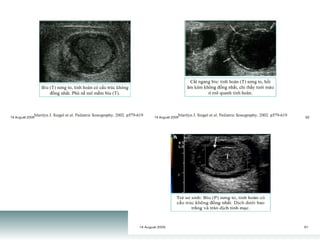

The document is an imaging department report discussing cardiac function measurements. It contains an abbreviation for the ratio of stroke volume (the amount of blood pumped out of the heart with each beat) to end diastolic volume, which is a measurement of cardiac output.